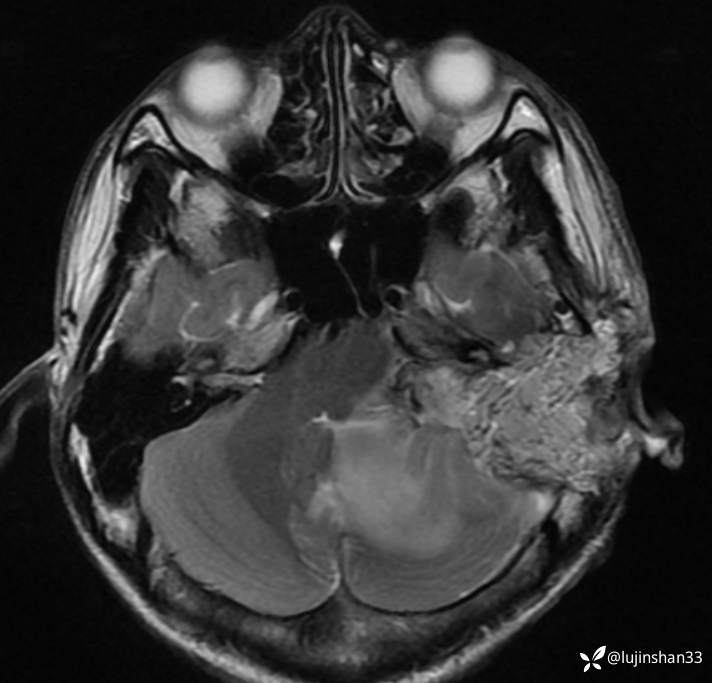

首次术前MRI